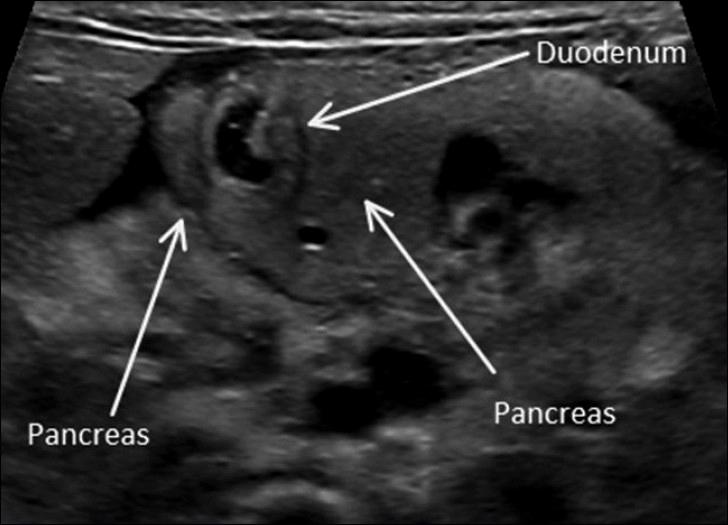

Annular Pancreas

6 year old present